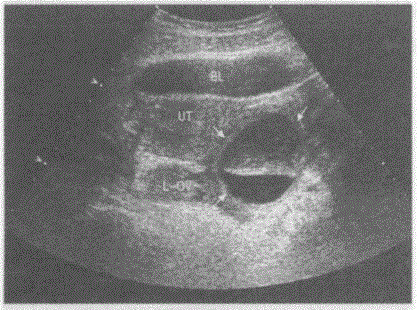

问题 临床资料:女,24岁,常规体检。妇科内诊:左附件区扪及一肿物,质软。 超声综合描述:左附件区可见圆形无回声区(箭头所示),边界清晰,形态规则,上半部透声不清亮,下半部透声清亮,两层间有一平面,随体位移动而变化。 超声提示:

选项 A.左卵巢囊性畸胎瘤(脂液分层征) B.左卵巢囊肿 C.左卵巢巧克力囊肿 D.左附件区包裹性积液

答案 A